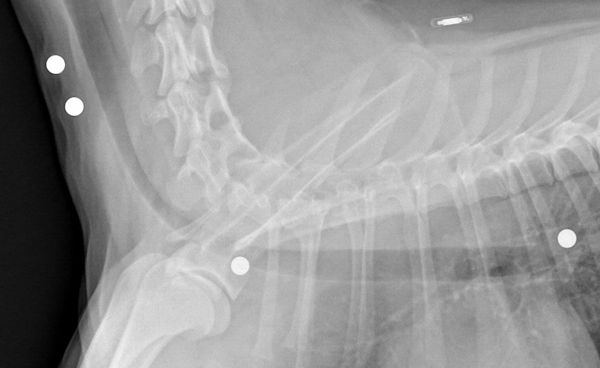

Little did anyone know, she carried some pretty severe scars hidden within her. On her first vet visit after we picked her up, we found buckshot lodged in her chest and along her left side (our vets are amazing PLUS they know we're somewhat obsessive about our animals so it was a REALLY thorough initial exam). Having found that, we feel extra lucky to be able to share our lives with this amazing little creature. We've added the x-ray below, in case anyone's interested.